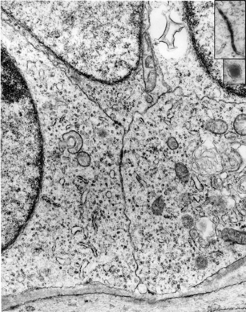

Fig. 1

Fig. 2

Fig. 3

Fig. 4